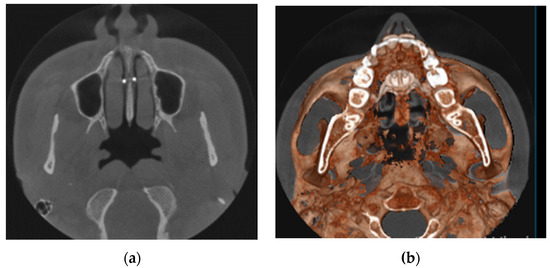

- MARPE associated with cortico-puncture therapy efficiently split the midpalatal suture in adults. The mean split at the anterior nasal spine (ANS) and posterior nasal spine (PNS) was 3.76 and 3.12 mm, respectively. The magnitude of the split at the PNS was smaller than at the ANS (by approximately 85% of the distance), showing that the opening of the midpalatal suture was almost parallel in the anteroposterior direction.

- MARPE therapy associated with cortico-puncture therapy had a positive outcome on midpalatal suture opening and maxillary advancement, but a medium molar inclination of 2.005° was also observed, suggesting that tooth movement cannot be avoided because of the anchorage of the MARPE device at the molar level.

- Our results suggest that non-surgical palatal expansion, assisted by micro-implants and cortico-puncture, is achievable and predictable in young adults. This occurs in safe conditions without the need for more complex surgical treatment.

- The combination of MARPE and the cortico-puncture method proved to be a non-surgical treatment option to correct maxillary transverse deficiency in young adult patients. Cortico-puncture was able to weaken the suture interdigitation, thus facilitating the split.